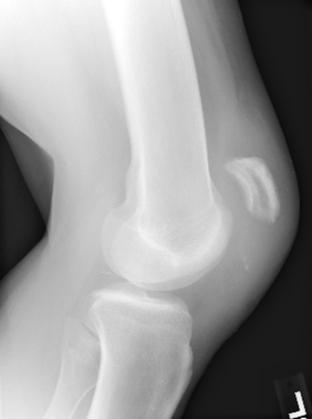

A long jumper lands in the sand pit and suddenly has severe pain and is unable to extend his knee. What is the diagnosis?